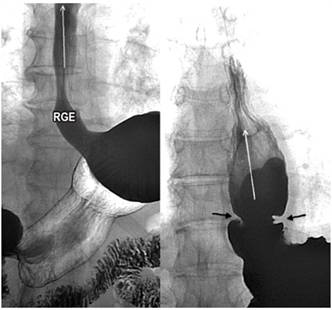

Reflujo gastroesofágico

El reflujo gastroesofágico es una afección presente en individuos normales que se torna patológica cuando se presenta con síntomas o complicaciones 6,7. Su fisiopatología es multifactorial y corresponde a un desequilibrio de los factores agresores y protectores (falla en la barrera y mecanismos de protección). Aunque el diagnóstico se realiza con la pH-metría de 24 horas, el esofagograma sugiere la presencia de reflujo con los cambios de posición (supino) y las maniobras de Valsalva, y permite la identificación de la presencia de hernias hiatales asociadas 6,7 (Figura 3).

La sensibilidad y la especificidad del esofagograma para el diagnóstico varía según la fase en la que se evalué y las complicaciones que se presenten. En la fase inicial de pie, su sensibilidad es baja, pero aumenta con los cambios de posición y las maniobras de Valsalva. Es así como, en pacientes con esofagitis moderada y severa, su sensibilidad varía de un 71% a un 85 %, con una baja tasa de detección de estenosis pépticas (43%) y un valor predictivo positivo de solo el 25% para la presencia de esófago de Barrett, pero un valor predictivo negativo del 99% 8,9,10.